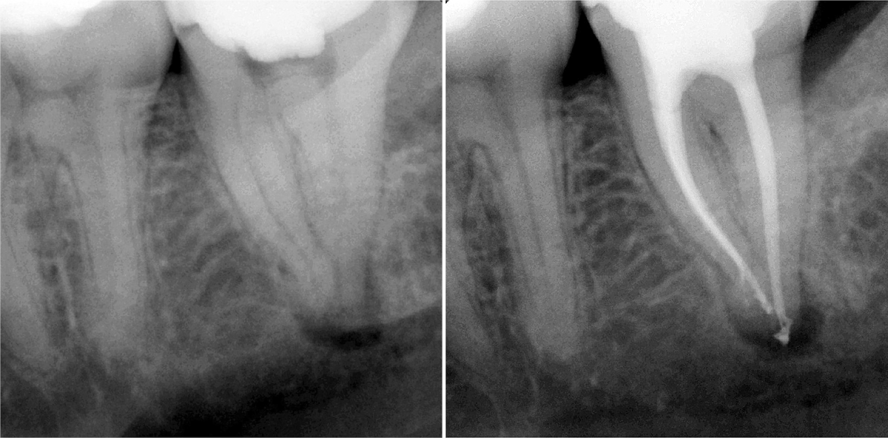

Fall 2 (Abb. 35a und b)

Im zweiten klinischen Fall handelt es sich um eine Pulpanekrose nach akutem Zahntrauma, die im Zuge einer akuten Exazerbation zu einem submukösen Abzess geführt hat. Der 8-jährige Patient hat ein nicht abgeschlossenes Wurzelwachstum. Die Restdentinstärke ist limitiert, die Wurzelscheide dünn und biomechanisch fragil, der apikale Durchmesser weit geöffnet bei ISO 100–120. Hier ist klinisch die Herausforderung, eine vollständige Reinigung des Wurzelkanalsystems zu erzielen ohne zusätzlichen Substanzverlust zu erzeugen. Daher wurde nach der Zugangsgestaltung von vestibulär die Aufbereitung und Reinigung mit der SAF mit 2 mm Durchmesser und 25 mm Länge durchgeführt. Das Protokoll war hier drei Minuten SAF auf voller Länge mit kontinuierlicher NaOCl-Spülung (3 %). Anschließend wurde der Kanal mit EDTA (17 %) gespült und die weitere Agitation des EDTA erfolgte mit der SAF bei ausgeschalteter Peristaltikpumpe für eine Minute. Dann wurde die Peristaltikpumpe der Aufbereitungseinheit wieder zugeschaltet und das NaOCl wurde für eine weitere Minute mit der SAF agitiert. Im Anschluss erfolgte die Trocknung des Wurzelkanals. Die Obturation erfolgte unter Sicht mit einem Kalziumsilikat-Zement (MTA) auf einer Länge von 3 mm. Anschließend wurde direkt ein Glasfaserstift mit einem selbstkonditionierenden Phosphorsäure-Methacrylat eingebracht.

Da in solchen Fällen von primär weitlumigen Wurzelkanälen durch die Anwendung der SAF eine effektive Reinigung, aber kein wesentlicher Zahnhartsubstanzabtrag erfolgt, ist dies ein neuer mikroinvasiver Therapieansatz in der Endododontie.